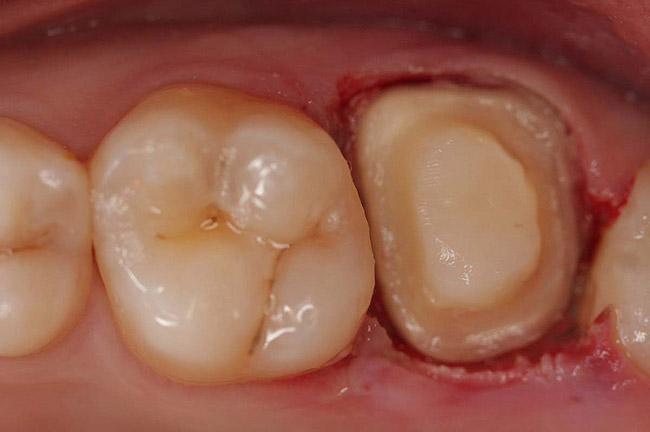

Figure 6  Endodontically treated maxillary right second molar.

Figure 6

Figure 7  Second molar with the palatal canal prepared for post placement.

Figure 7

A Class IIIN maxillary left second molar required restoration (Figure 6). Four canals, a chamber space, and little cross section of tooth structure were in the gingival third. Gutta-percha was removed with a Peeso reamer supplied in the C-1 kit. The canal was shaped with a bur in the kit, which was the same size as the corresponding post (Figure 7). The tooth structure was bonded with Brush & Bond™ (Parkell, www.parkell.com), and then the resin cement was spun into the canal with a lenticulo spiral. A C-1 white post was placed in the palatal canals (Figure 8). The C-1 White Post is a fiber-reinforced composite post, which flexes at the same rate as dentin to minimize root stresses.

Core build-up was completed with Absolute Dentin™ (Parkell, www.parkell.com) dual-cure high-strength core composite. There are variations on color and how materials cure. For example, Light-Core™ (Bisco, www.bisco.com) is a light-cured blue material, Encore® (Centrix, www.centrixdental.com) is a self-cure white material, and Para Core (Coltène Whaledent, www.coltene.com) is a dual-cure white or dentin-colored material. Material was placed directly and light-cured for 40 seconds (Figure 9). Final preparation for a PFM was completed (Figure 10). The final crown was placed (Figure 11).